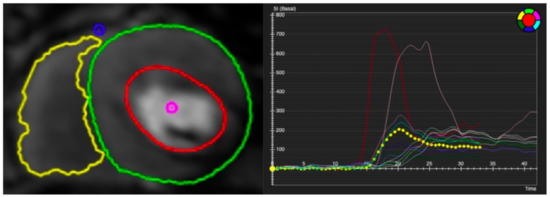

Likewise, in dilated cardiomyopathy (DCM), vasodilator stress-rest perfusion is performed to determine the presence of inducible ischemia [13]. Even if DCM is considered a non-ischemic myocardial disease, the affected patients usually show diffuse myocardial hypoperfusion (Figure 8) [85]. A recent quantitative stress CMR study showed that DCM patients had significantly reduced stress MBF and global MPR with increased rest MBF versus normal controls, likely due to an increased hemodynamic load and structural alteration of the coronary microvasculature [86,87]. Furthermore, coronary vasodilatory dysfunction was correlated with worse LV systolic function [86]. The results from stress CMR revealed the myocardial damage in DCM was caused by an impaired coronary vasodilatory reserve, rather than chronic myocardial hypoperfusion. In the future, CMD detected by stress CMR may serve as the innovative target in DCM patients, and the long-term prognosis needs to be investigated.

Figure 8.

Quantitative stress CMR examination of dilated cardiomyopathy. Female patient in her 60s with dilated cardiomyopathy and phospholamban genetic mutation. Patient underwent stress CMR, having presented with symptoms and signs of heart failure. Top left panel of six images shows quantitative perfusion images with reduced global myocardial blood flow (MBF) during stress. Lower left panel of stress perfusion images shows no stress-induced perfusion defect. Stress MBF and myocardial perfusion reserve bulls-eye plots objectively demonstrate this low perfusion. Coronary computed tomography multiplanar reformat images of the three main coronary arteries show no significant coronary artery disease.